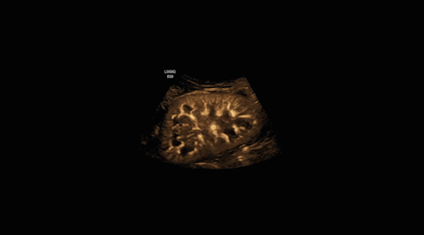

Dr. Ralf Menkhaus ve çalışma arkadaşları, bir süredir GE Sağlık’ın fetüs beyin değerlendirmesini ve ölçümlerini otomatikleştiren yapay zekâ aracı SonoCNS’yi kullanıyor.

Fetüs Tıbbı Uzmanı Dr. Ralf Menkhaus ana rahmindeki bebekler için sorun belirtisi olup olmadığını saptamak üzere ultrason görüntülerini inceliyor. Örneğin, omuriliği etkileyen bir nöral tüp defekti olan ve doktorların fetal beyindeki değişiklikler gibi ipuçlarına dayanarak hamileliğin yaklaşık 20. haftasında teşhis edilebilen spina bifida gibi. Ancak fetal beyin ölçümleri, tecrübeli doktorların birden çok metriği dikkate almak zorunda olduğu ve kesinliği düşük sayılabilecek bir bilim. Bir sonografi uzmanının değerlendirmesi diğerinden farklı olabildiğinden, hatalı veya gecikmiş tanılara yol açabiliyor. Menkhaus, GE Sağlık‘ın fetal beyin değerlendirmesini ve ölçümlerini otomatikleştiren yapay zekâ aracı SonoCNS teknolojisi ile süreci basitleştirebileceğini duyduğunda oldukça rahatladığını belirtiyor. SonoCNS, GE Sağlık‘ın bulut tabanlı uygulama geliştirme, veri depolama ve analiz platformu Edison aracılığıyla eğitildi. Menkhaus, bu teknolojinin daha az tecrübeli jinekologlar için özellikle faydalı olduğunu belirtiyor: “Artık, tek bir düğmeye basarak doğru ve güvenilir ölçümlere erişebilecekler.”